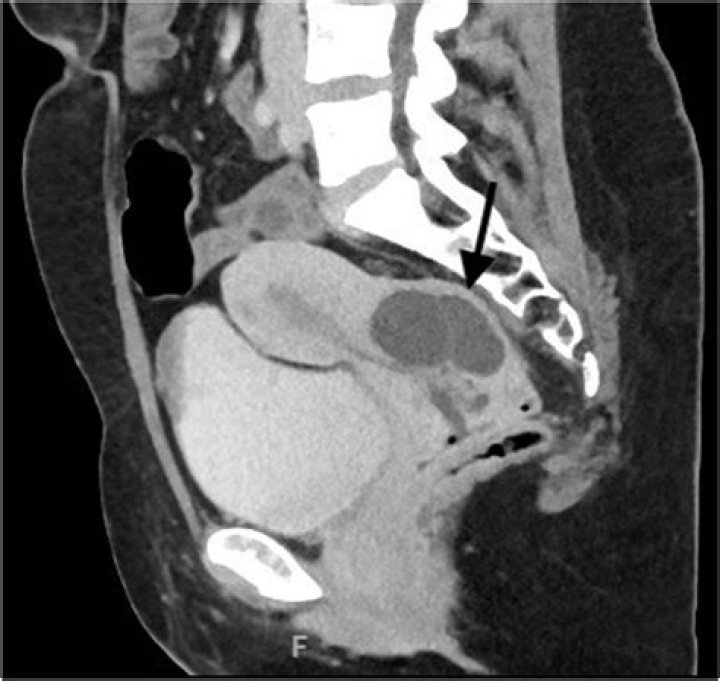

Nabothian cysts are mucus-filled cysts that occur on the surface of the cervix. They are usually 0.2 to 0.3 cm in diameter, but they can exceed 1 cm in diameter. In most cases, nabothian cysts reflect the physiological changes in the cervix, but they are sometimes related to chronic cervicitis.

Nabothian cysts (also called mucinous retention cysts or epithelial cysts) are common and benign and are considered a normal feature of the adult cervix (Figure 1, C). Many women have multiple cysts. They may be translucent or opaque, whitish to yellow, and range from a few millimeters to 3 to 4 cm in diameter.